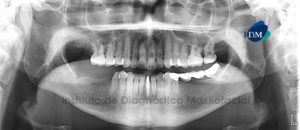

Paciente femenino, 37 años de edad, es referido al Instituto de Diagnóstico Maxilofacial (IDM) para evaluación general. A la evaluación de la radiografía panorámica se